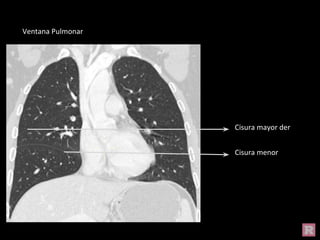

Cisura mayor der

Cisura menor

Ventana Pulmonar